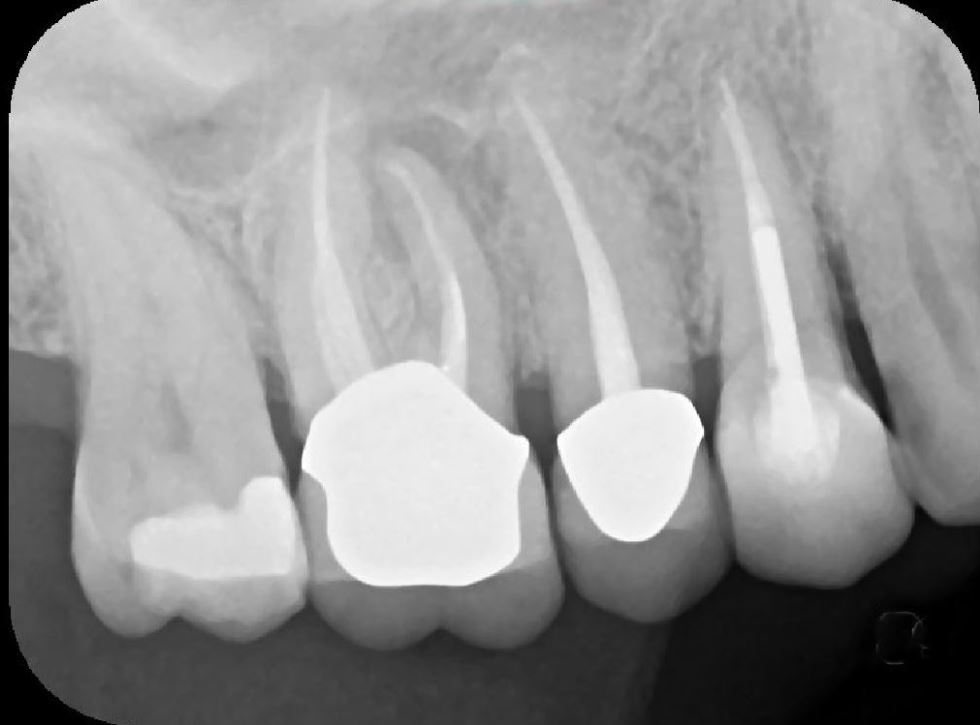

X-Ray 3: How many caries are present?

(Required)

X-Ray 3: How many PAP's are present?